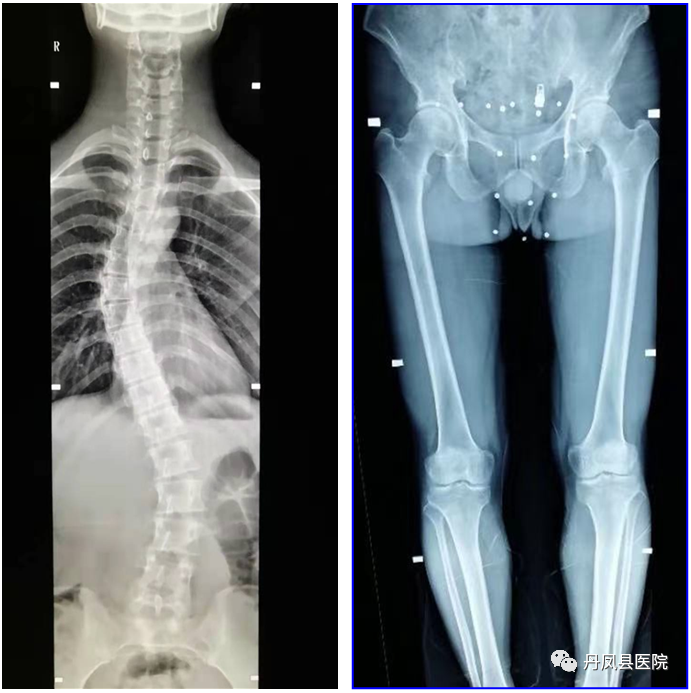

普通放射开展常规各部位DR摄影检查、床旁摄影、C型壁术中透视摄影,食管造影、上消化道造影、结肠造影、全消化道造影、静脉尿路造影、膀胱尿道造影、子宫输卵管造影、T型管造影、各类窦道造影及四肢全长、脊柱全长拼接摄影检查。![微信图片_20210419163637.jpg]()

脊柱全长拼接、双下肢全长拼接